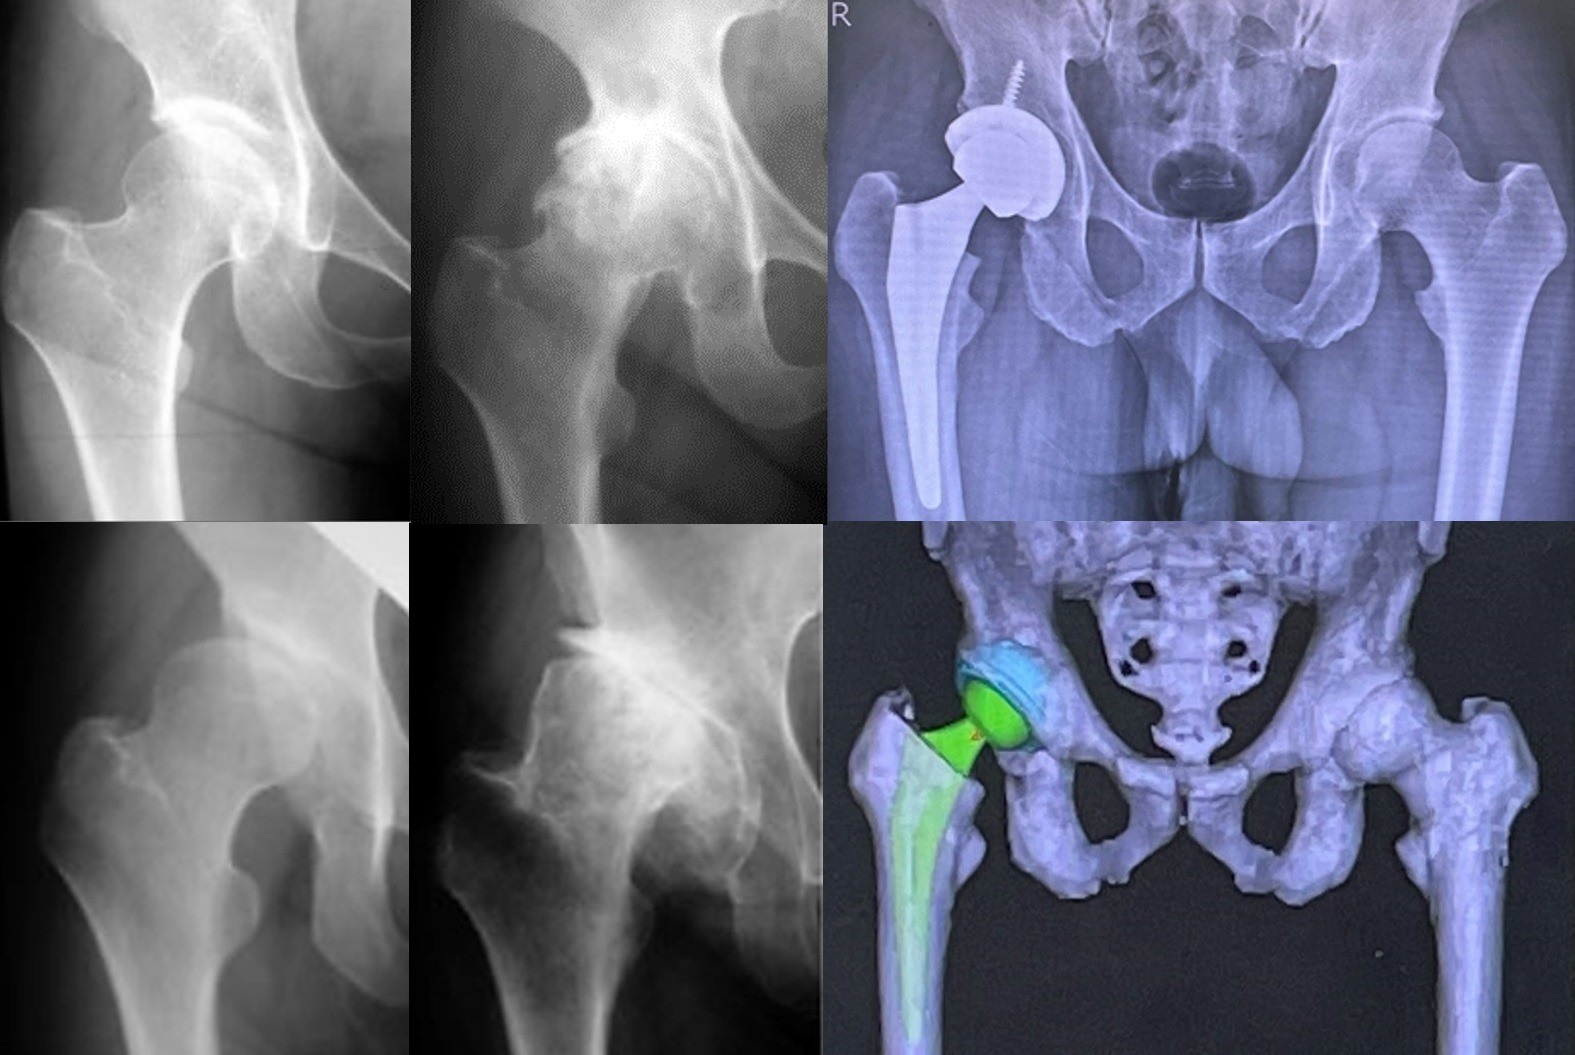

• 変形性股関節症の症状と治療

人工関節外科

変形性股関節症の症状と治療